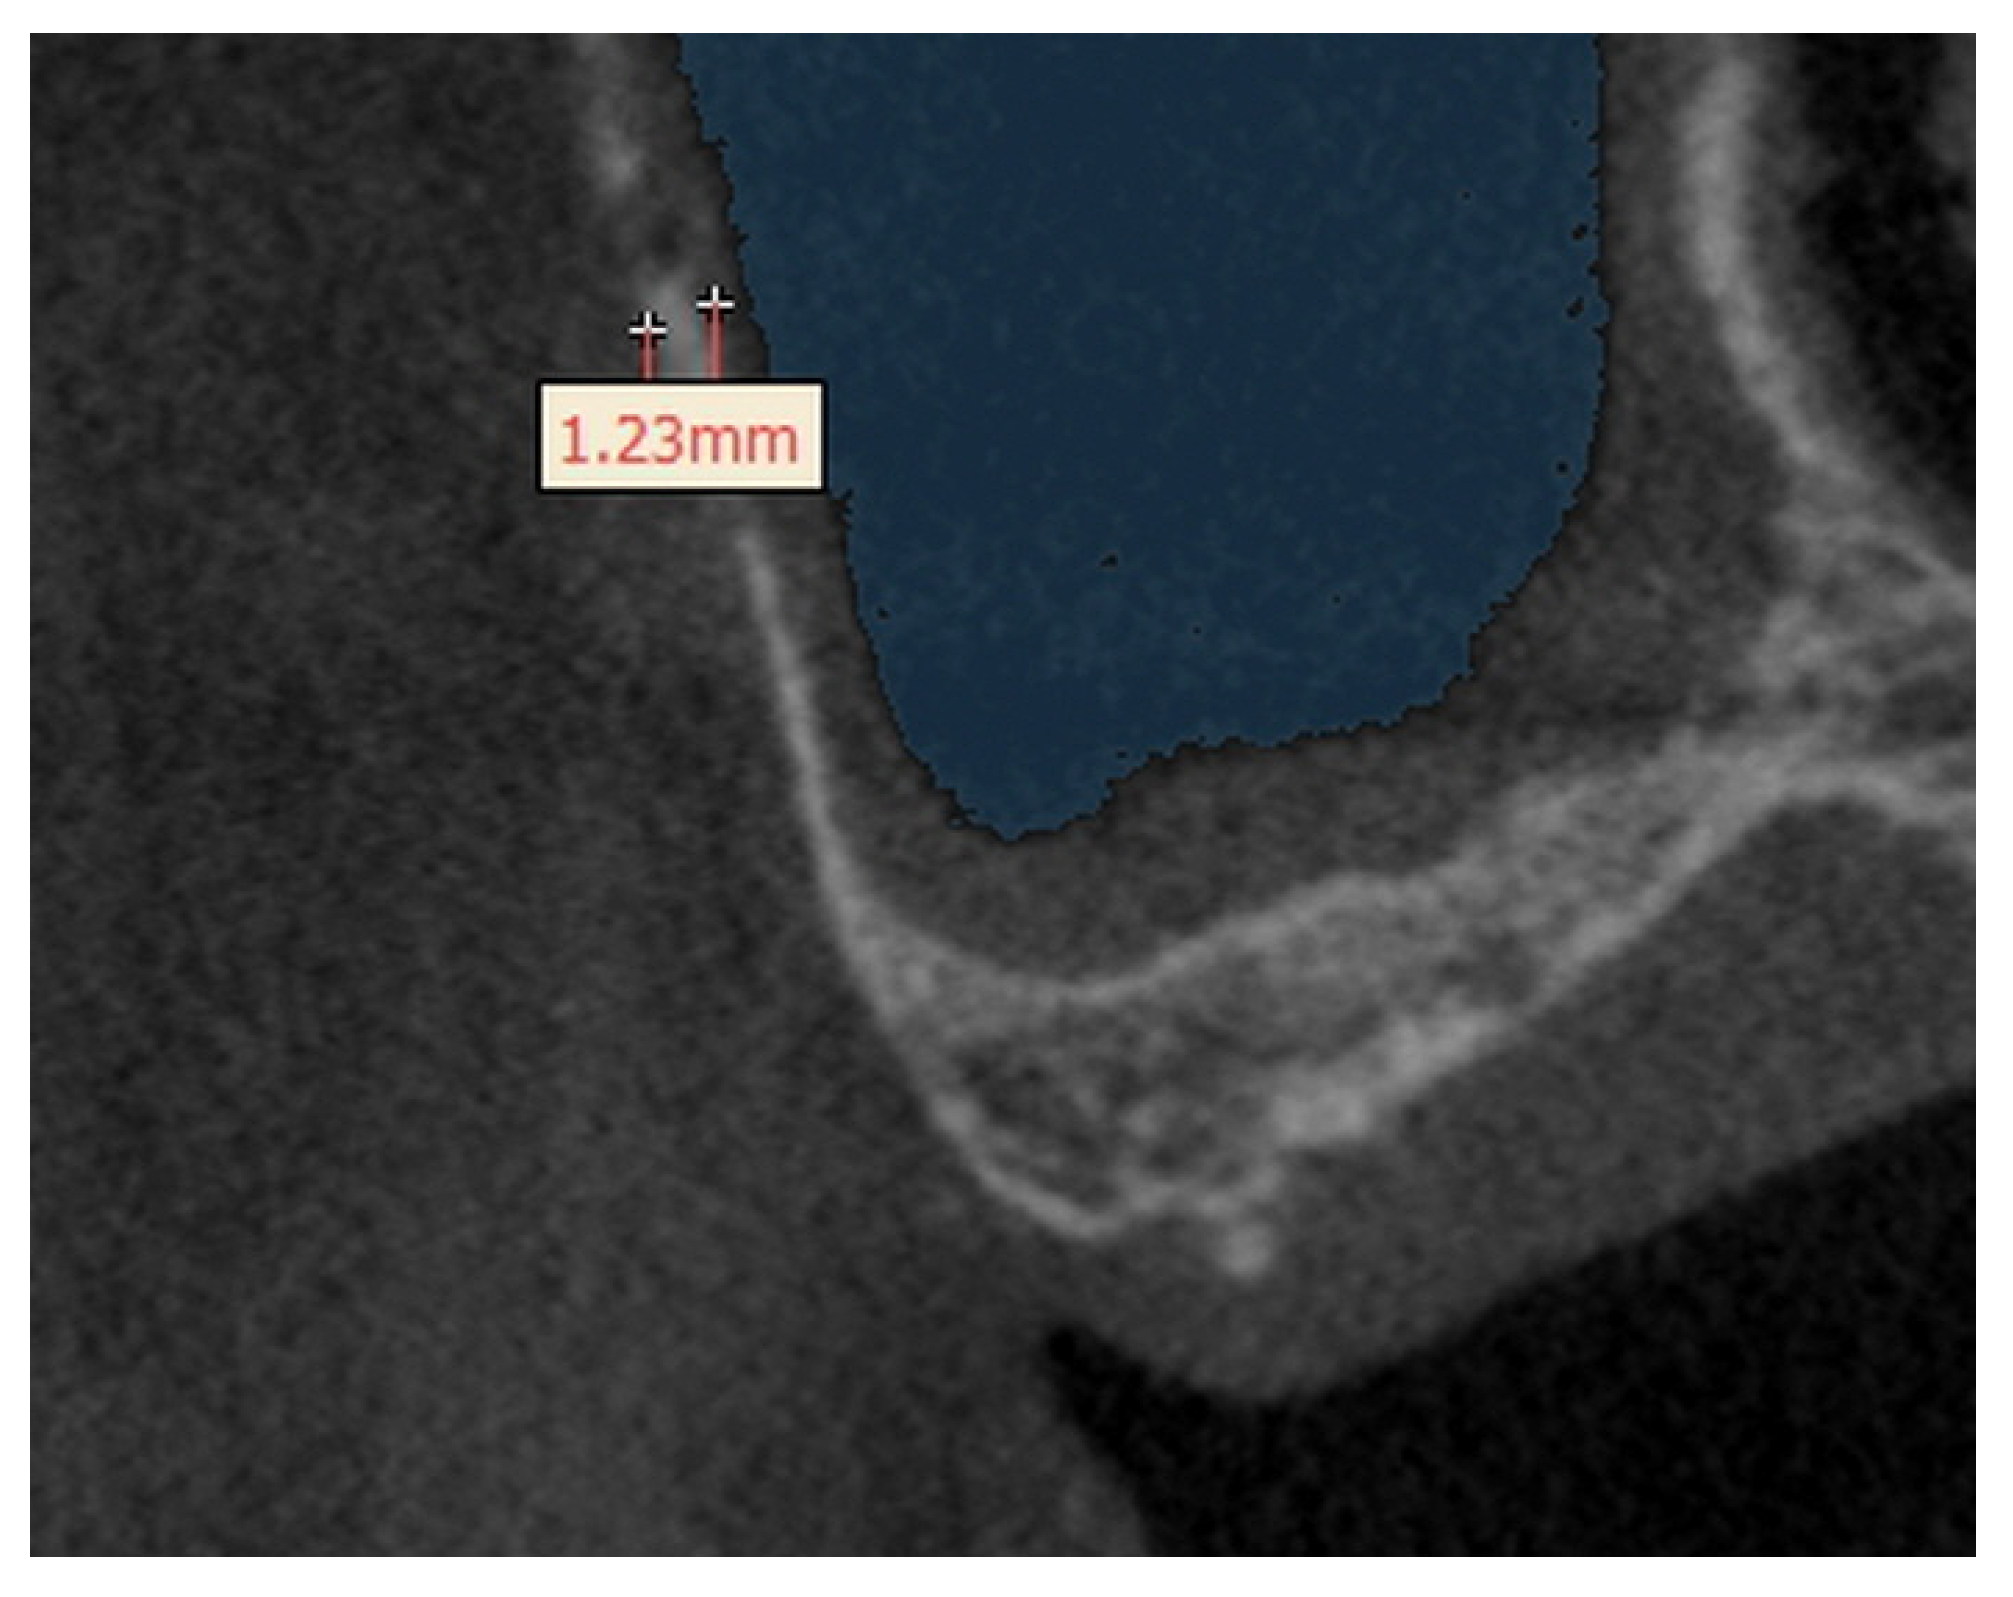

3.4. The Height of Residual Bone

| Height from the Sinus Floor to Residual Crest | |||

| Mean ± S.D. | Maximum | Minimum | |

| Height | 2.97 ± 1.08 | 4.98 | 0.93 |

| (Mean ± S.D.) | |||

| Gender | p-Value | ||

| Male | Female | ||

| Height (mm) | 2.92 ± 1.14 | 3.05 ± 1.00 | 0.595 |